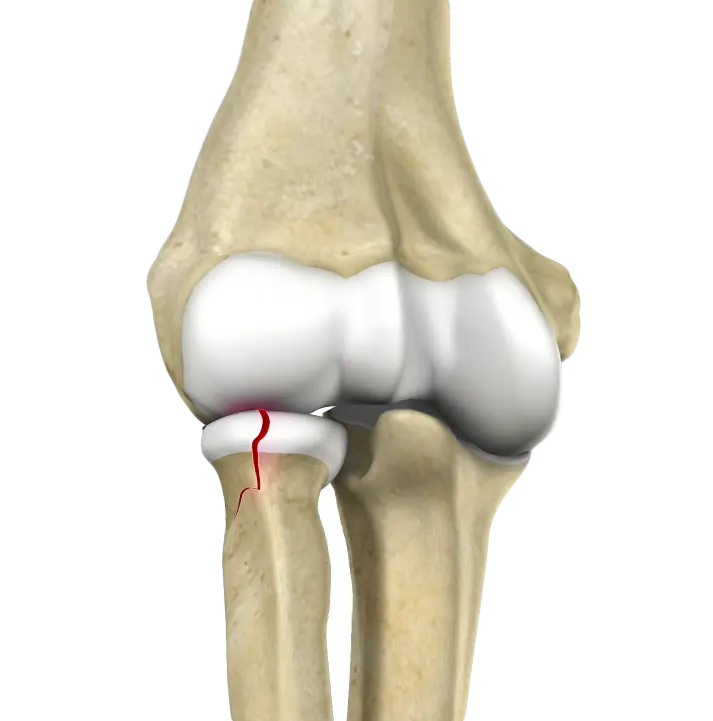

Distal Humerus Fractures of the Elbow

Injury in the distal humerus can cause impairment in the function of the elbow joint.

Radial Head Fractures of the Elbow

Radial head fractures are very common and occur in almost 20% of acute elbow injuries.